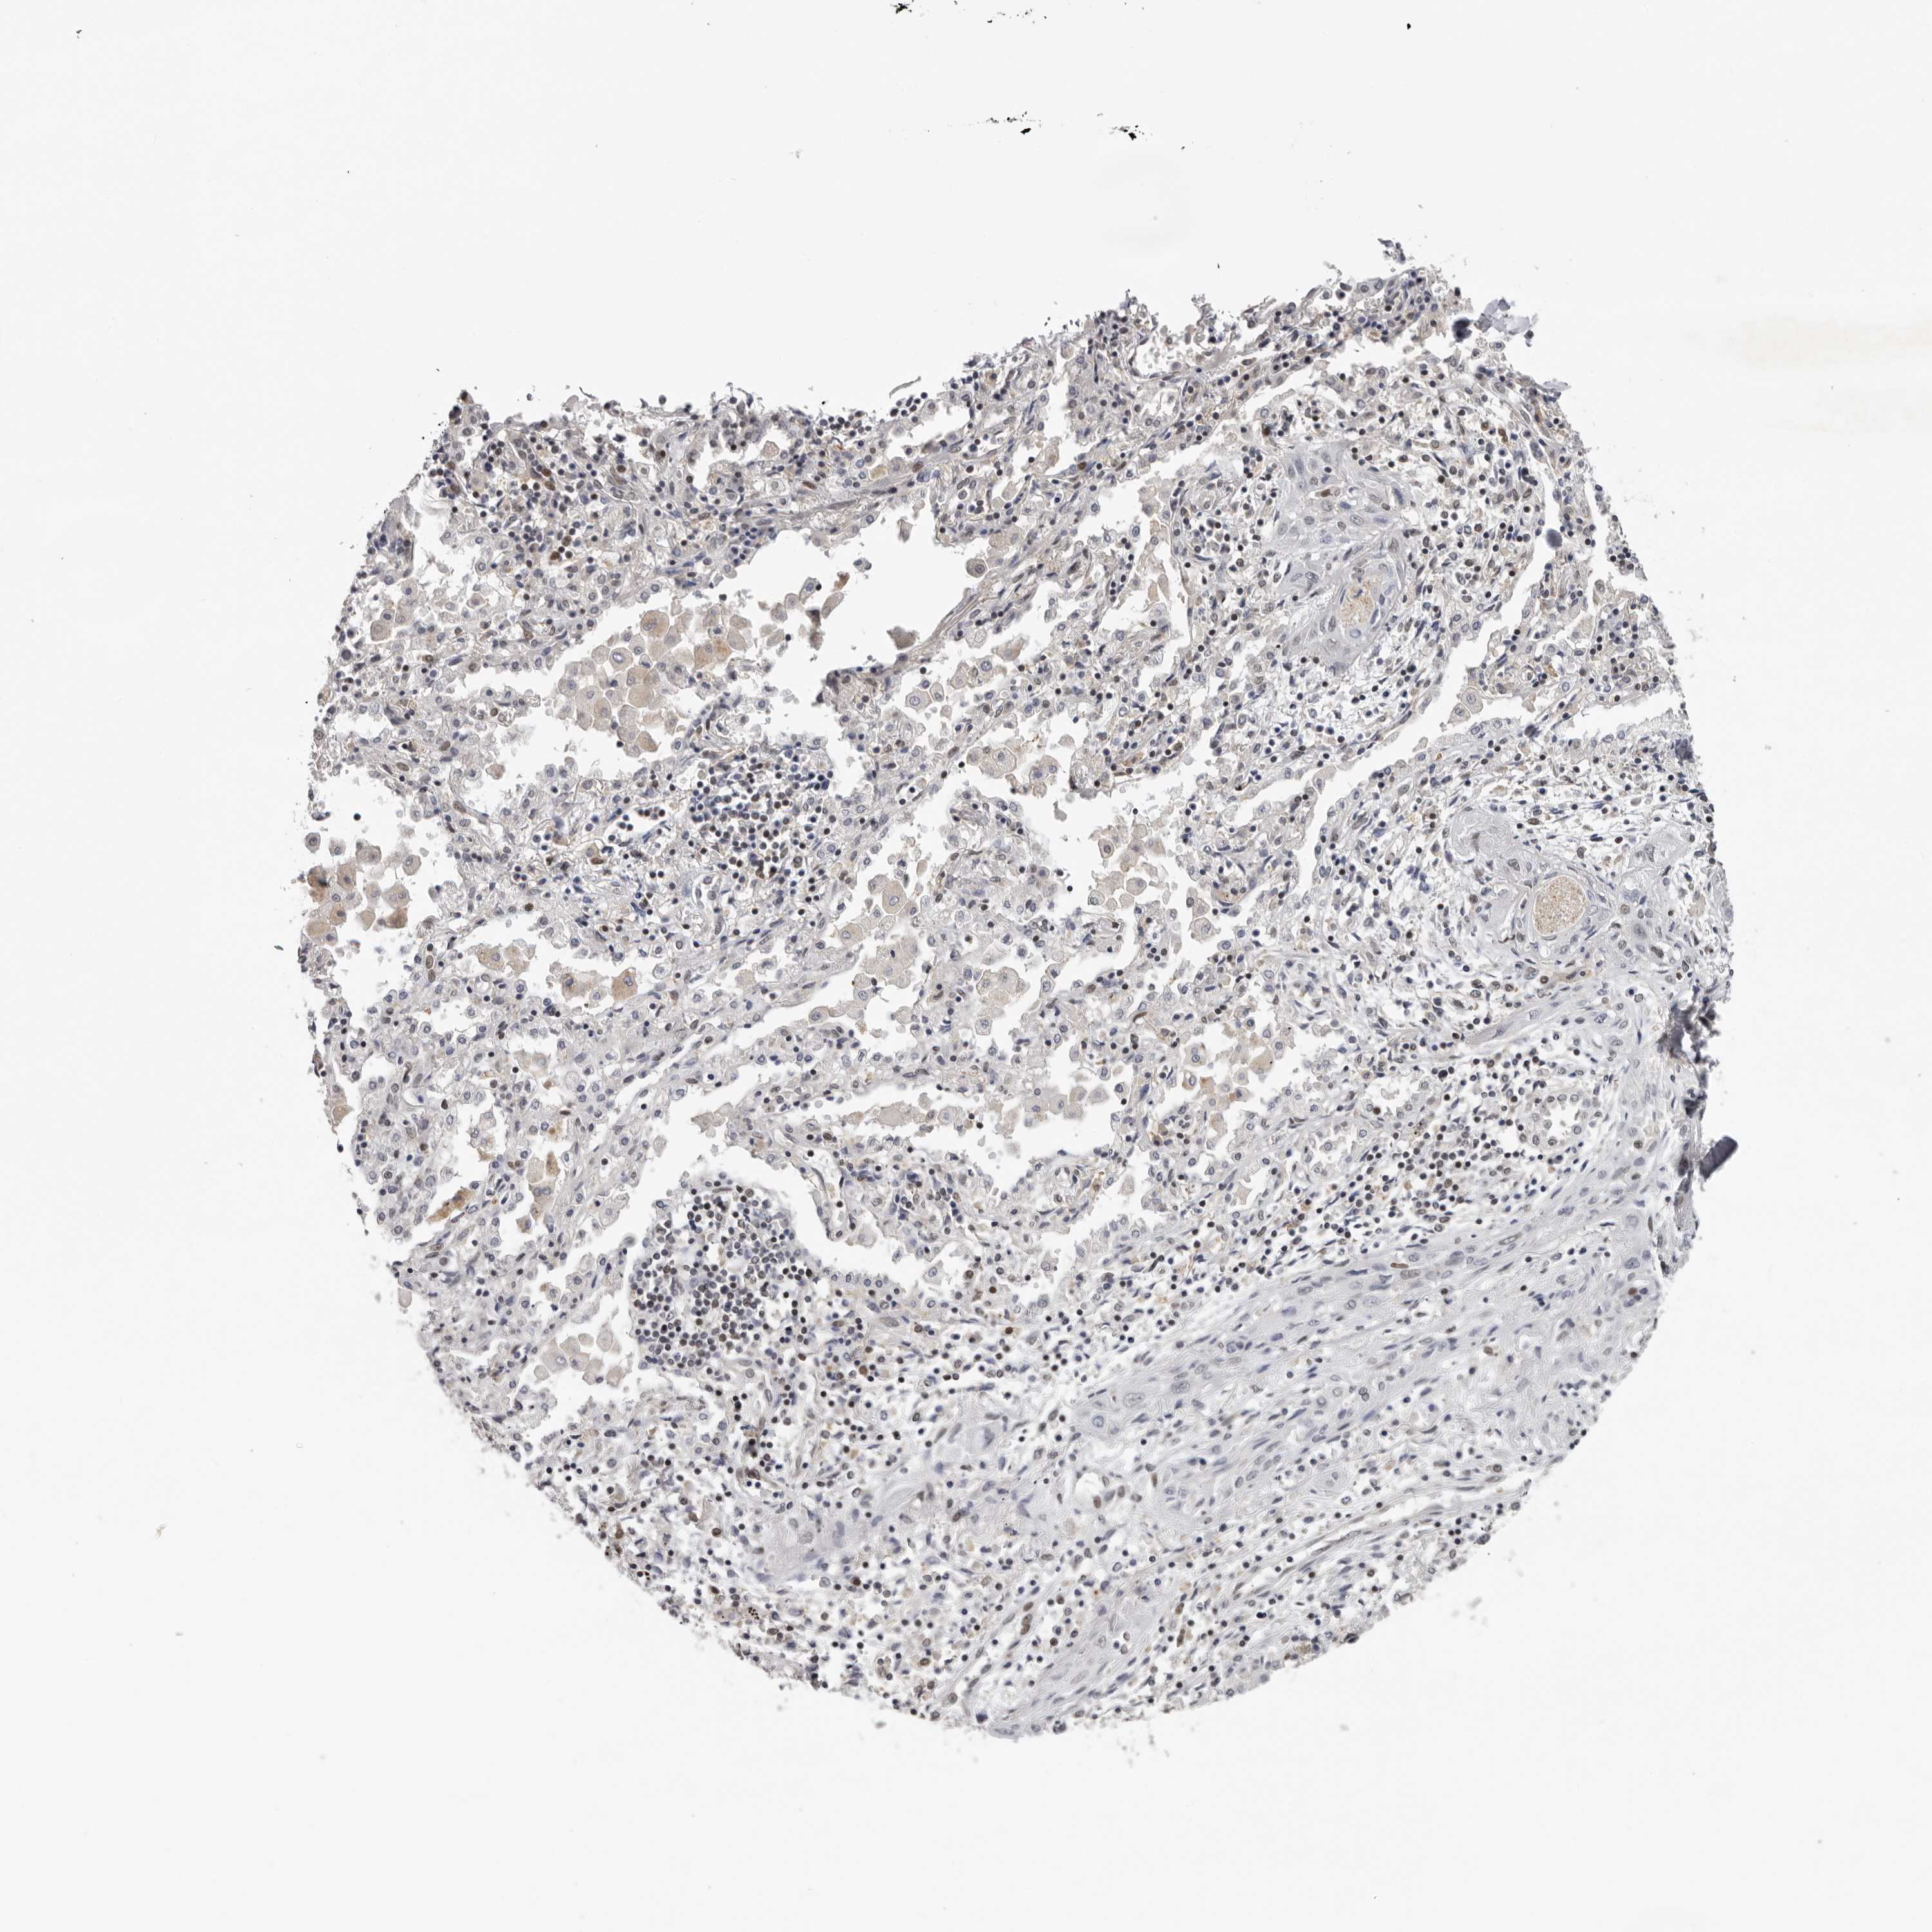

CANCER LUNG CANCER Show tissue menu

LUAD TCGA LUAD VALIDATION LUSC TCGA LUSC VALIDATION PROTEIN LUAD CPTAC PROTEIN LUSC CPTAC PROTEIN EXPRESSION

ANTIBODIES

AND

VALIDATION